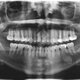

Radiografia

HISTORIA DE LA RADIOLOGÍA ORAL Y MAXILOFACIAL